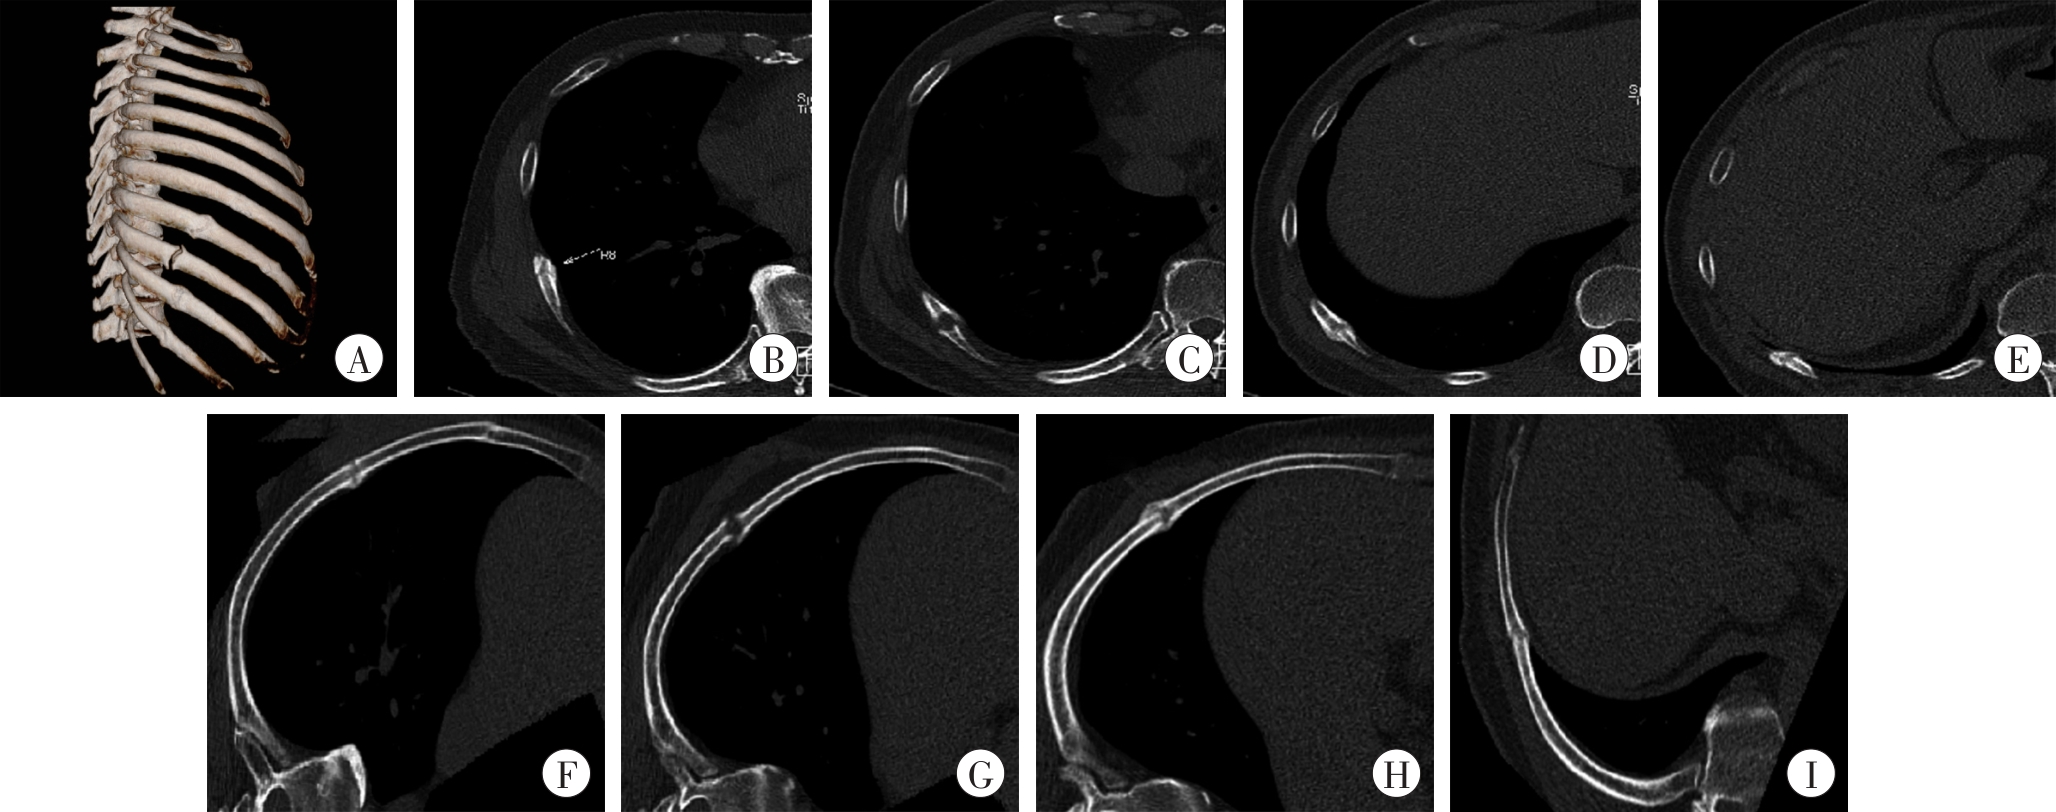

| 图3 3种图像后处理技术的比较 男性患者,59岁,胸部外伤5个月余。A:右侧肋骨VR图像;B:右侧第8肋骨MPR图像;C:右侧第9肋骨MPR图像;D:右侧第10肋骨MPR图像;E:右侧第11肋骨MPR图像;F:右侧第8肋骨CPR图像;G:右侧第9肋骨CPR图像;H:右侧第10肋骨CPR图像;I:右侧第11肋骨CPR图像。  |

| Fig. 3 Comparison of three image post-processing techniques |